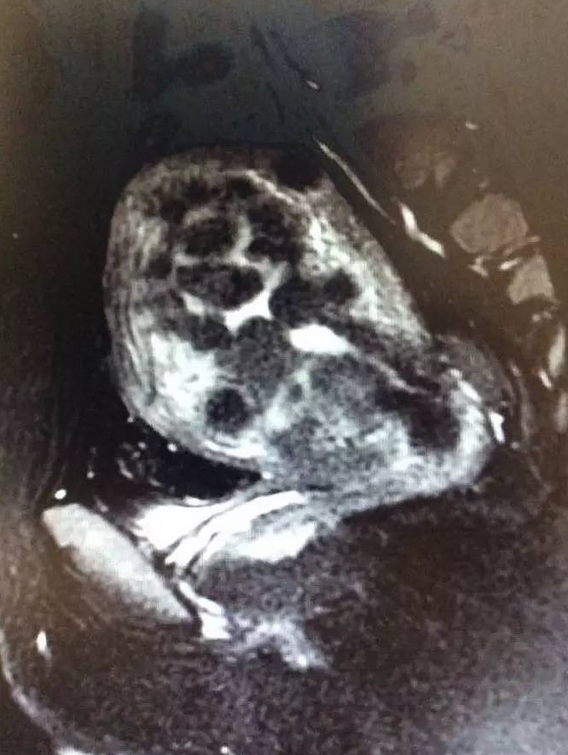

图1. 适合做磁波治疗的子宫肌瘤

(1)在治疗的靶区之前是否存在着肠管等影响超声波通透的肠管,超声波对于空腔脏器是容易产生反射和折射的,所以若是在子宫前方存在着肠管等,超声波就不能穿透。当然有的时候通过直肠内打胶或者推挤膀胱的方式也可以将肠管排空,后倾后屈的子宫往往不容易成功。图1中治疗的靶区子宫紧贴着腹壁,超声波能量容易通过,就是适合于磁波治疗的情况。图2中子宫后倾,前方有不少肠管组织在,肠管会影响超声波的穿透,就不是特别适合做磁波治疗。